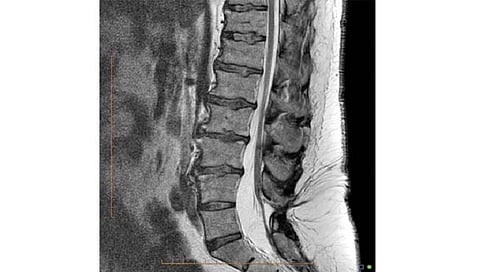

तिने मुलाच्या एमआरआय नोटस्ना क्रमानुसार चॅटजीपीटीमध्ये प्लग केले. चॅटजीपीटीने नोट केले की लेक्स पालथी मांडी घालून बसू शकत नाही. त्याचे कारण मेंदूच्या संरचनात्मक भागात समस्या असू शकते. त्याने आपल्या निष्कर्षामध्ये सांगितले की, त्याला न्यूरॉलॉजिकल सिंड्रोम 'टेथर्ड कॉर्ड' आहे. त्यामध्ये मणका आसपासच्या ऊतींशी जोडलेला असतो. हे निदान झाल्यावर त्याच्या मणक्यावर शस्त्रक्रिया करण्यात आली. त्यानंतर आता तो ठीक होत आहे.